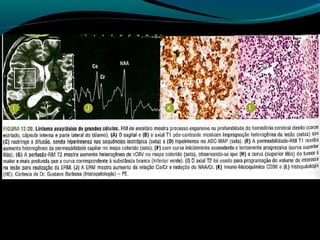

Astrocitoma difuso (GRAU II OMS)

RM:

Discreta redução do NAA;

Aumento do Co;

Aumento da relação Mi/Cr;

Valores do coeficiente de difusão aparente aumentados;

Baixa perfusão;

Recomendações:

RM associada às técnicas (ERM, difusão, perfusão)

método de escolha para detecção, controle evolutivo,

e controle pós-operatório;

Glioblastoma

Redução do NAA

Aumento do Co

Redução da razão Mi/Cr

Picos de lipídeos e lactato

Centro necrótico não restringe à difusão;

Na perfusão: aumento do CRBv máximo;

OBS: capacidade invasiva impede ressecabilidade total;